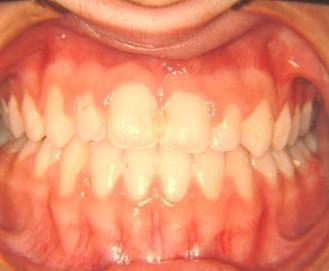

Δεύτερη περίπτωση

031

Η σημασία της στοματικής υγιεινής και ορθοδοντικής πρόληψης

Aσθενής με έντονο υπογναθισμό της άνω γνάθου και προγναθισμό της κάτω.

Υπεβλήθη σε συνδυασμό προχειρουργικής ορθοδοντικής θεραπείας, γναθοπροσωπικής χειρουργικής και μεταχειρουργικής ορθοδοντικής θεραπείας λόγω της ηλικίας της Σταυροειδής σύγκλειση - Προσωπική ασυμμετρία

Διόρθωση σταυροειδούς συγκλείσεως σε ηλικία 8 ετών απέτρεψε προσωπική ασυμμετρία. Η έγκαιρη θεραπεία σε οδοντοσκελετικά προβλήματα και η σκελετική διόρθωση της σχέσης των δύο γνάθων πρέπει να γίνεται στην περίοδο της σχολικής ηλικίας και έχουν εμφανή αποτελέσματα στο πρόσωπο και στην ψυχολογία του παιδιού